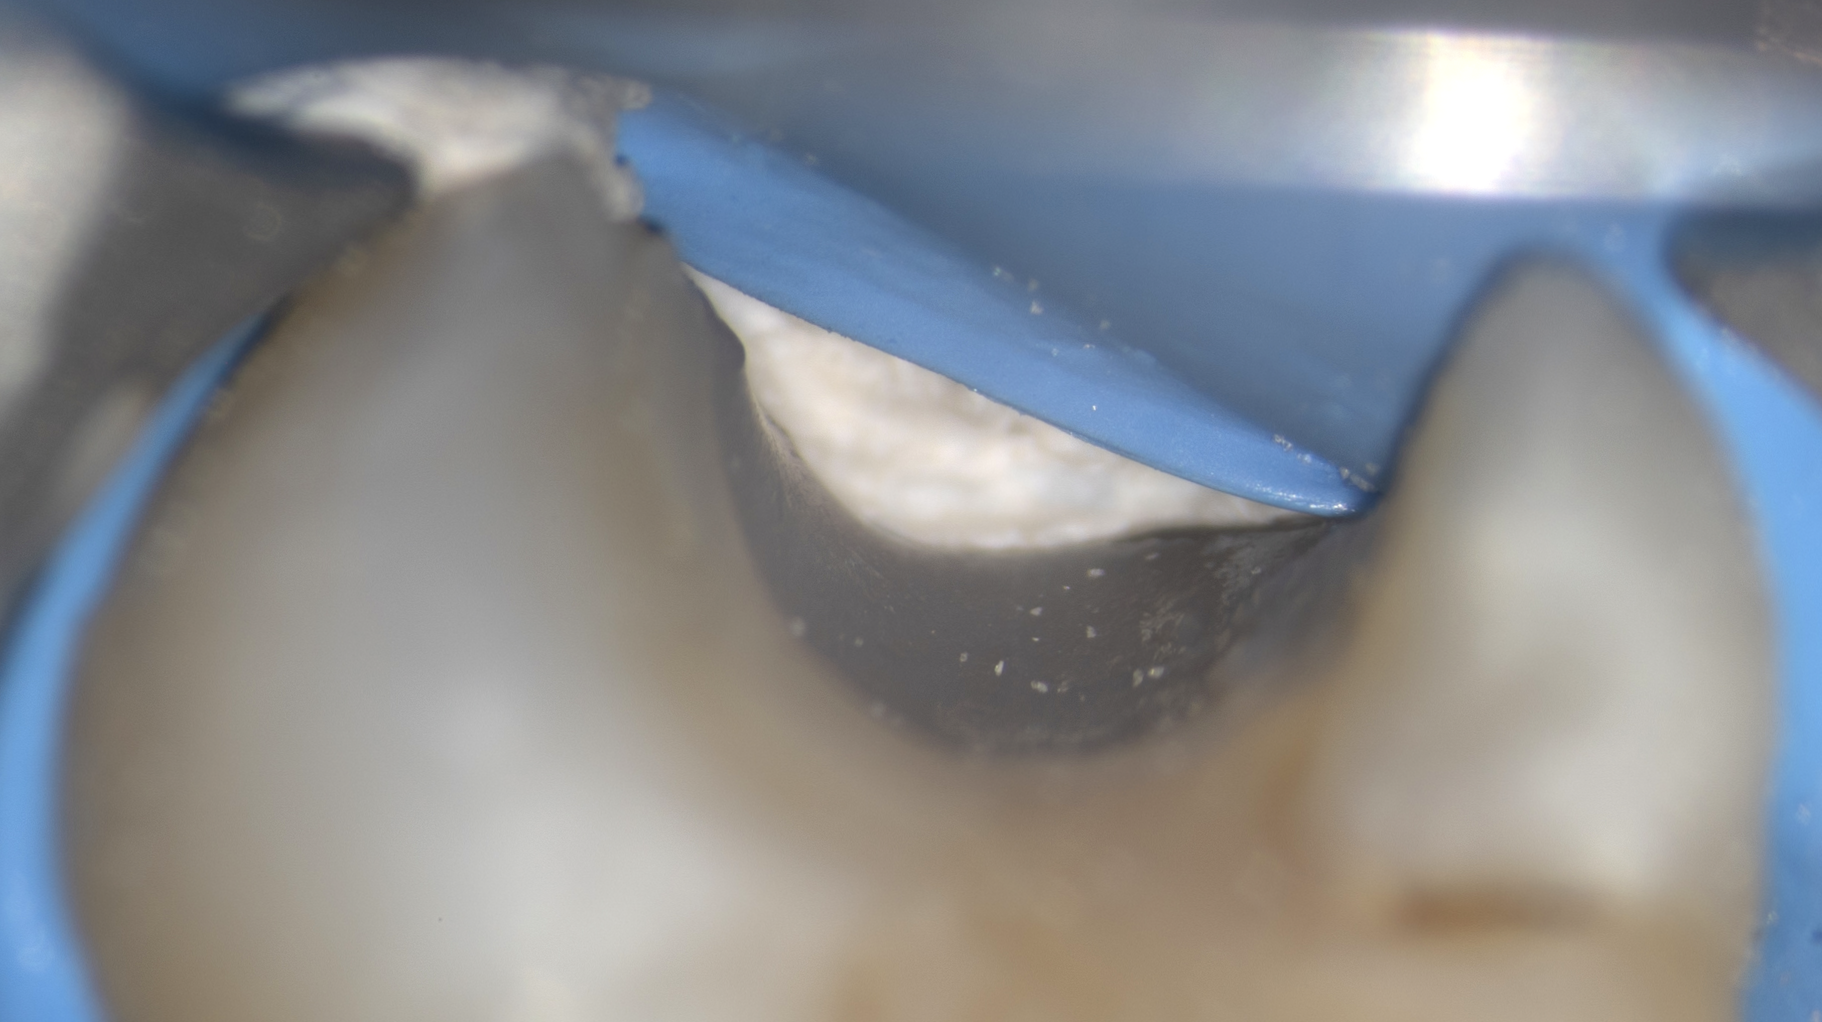

Cas clinique d’une 17 (2e molaire en haut à droite)

Coiffage pulpaire indirect : 96,4% de taux de succès

Cas clinique

Coiffage pulpaire direct : 90,4% de taux de succès

Cas clinique

Pulpotomie partielle : 88,2% de taux de succès

Cas clinique

Pulpotomie totale : 91,3% de taux de succès